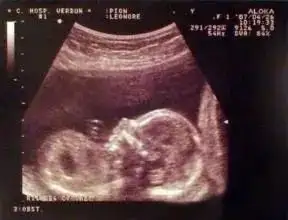

这个决定是艰难的,但为了至少能保住一个,我还是选择了减胎。孕22周的那一天,我在完全清醒的状态下做了手术,我一直眼含泪水目不转睛地盯着超声波的屏幕,因为在那里,我要跟我亲爱的二宝做最后的告别。